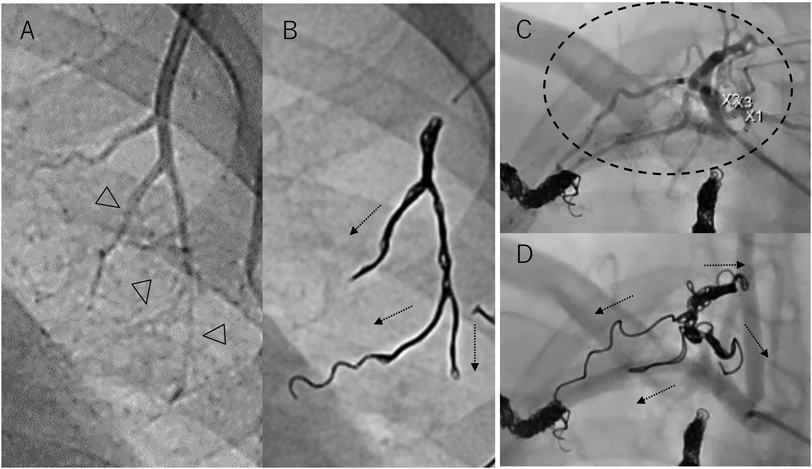

a.複雑に分枝した血管

Fig. 2 複雑に分枝した血管へのコイル塞栓

A, B)18歳フォンタン術後患者における外側胸動脈の塞栓.末梢分枝の径は1 mm以下であったが,Target™ XXLコイル6 mm×40 cm, 5 mm×20 cmでそれぞれの分枝(矢頭)に入り込んで(矢印)塞栓した.C, D)11歳フォンタン術後患者における複雑に分枝した体肺側副動脈(点線円)の塞栓.分枝の血管径は1~1.5 mmであったが,Target™ XXL 5 mm×20 cm×2本で分枝に入り込むように塞栓した(矢印).